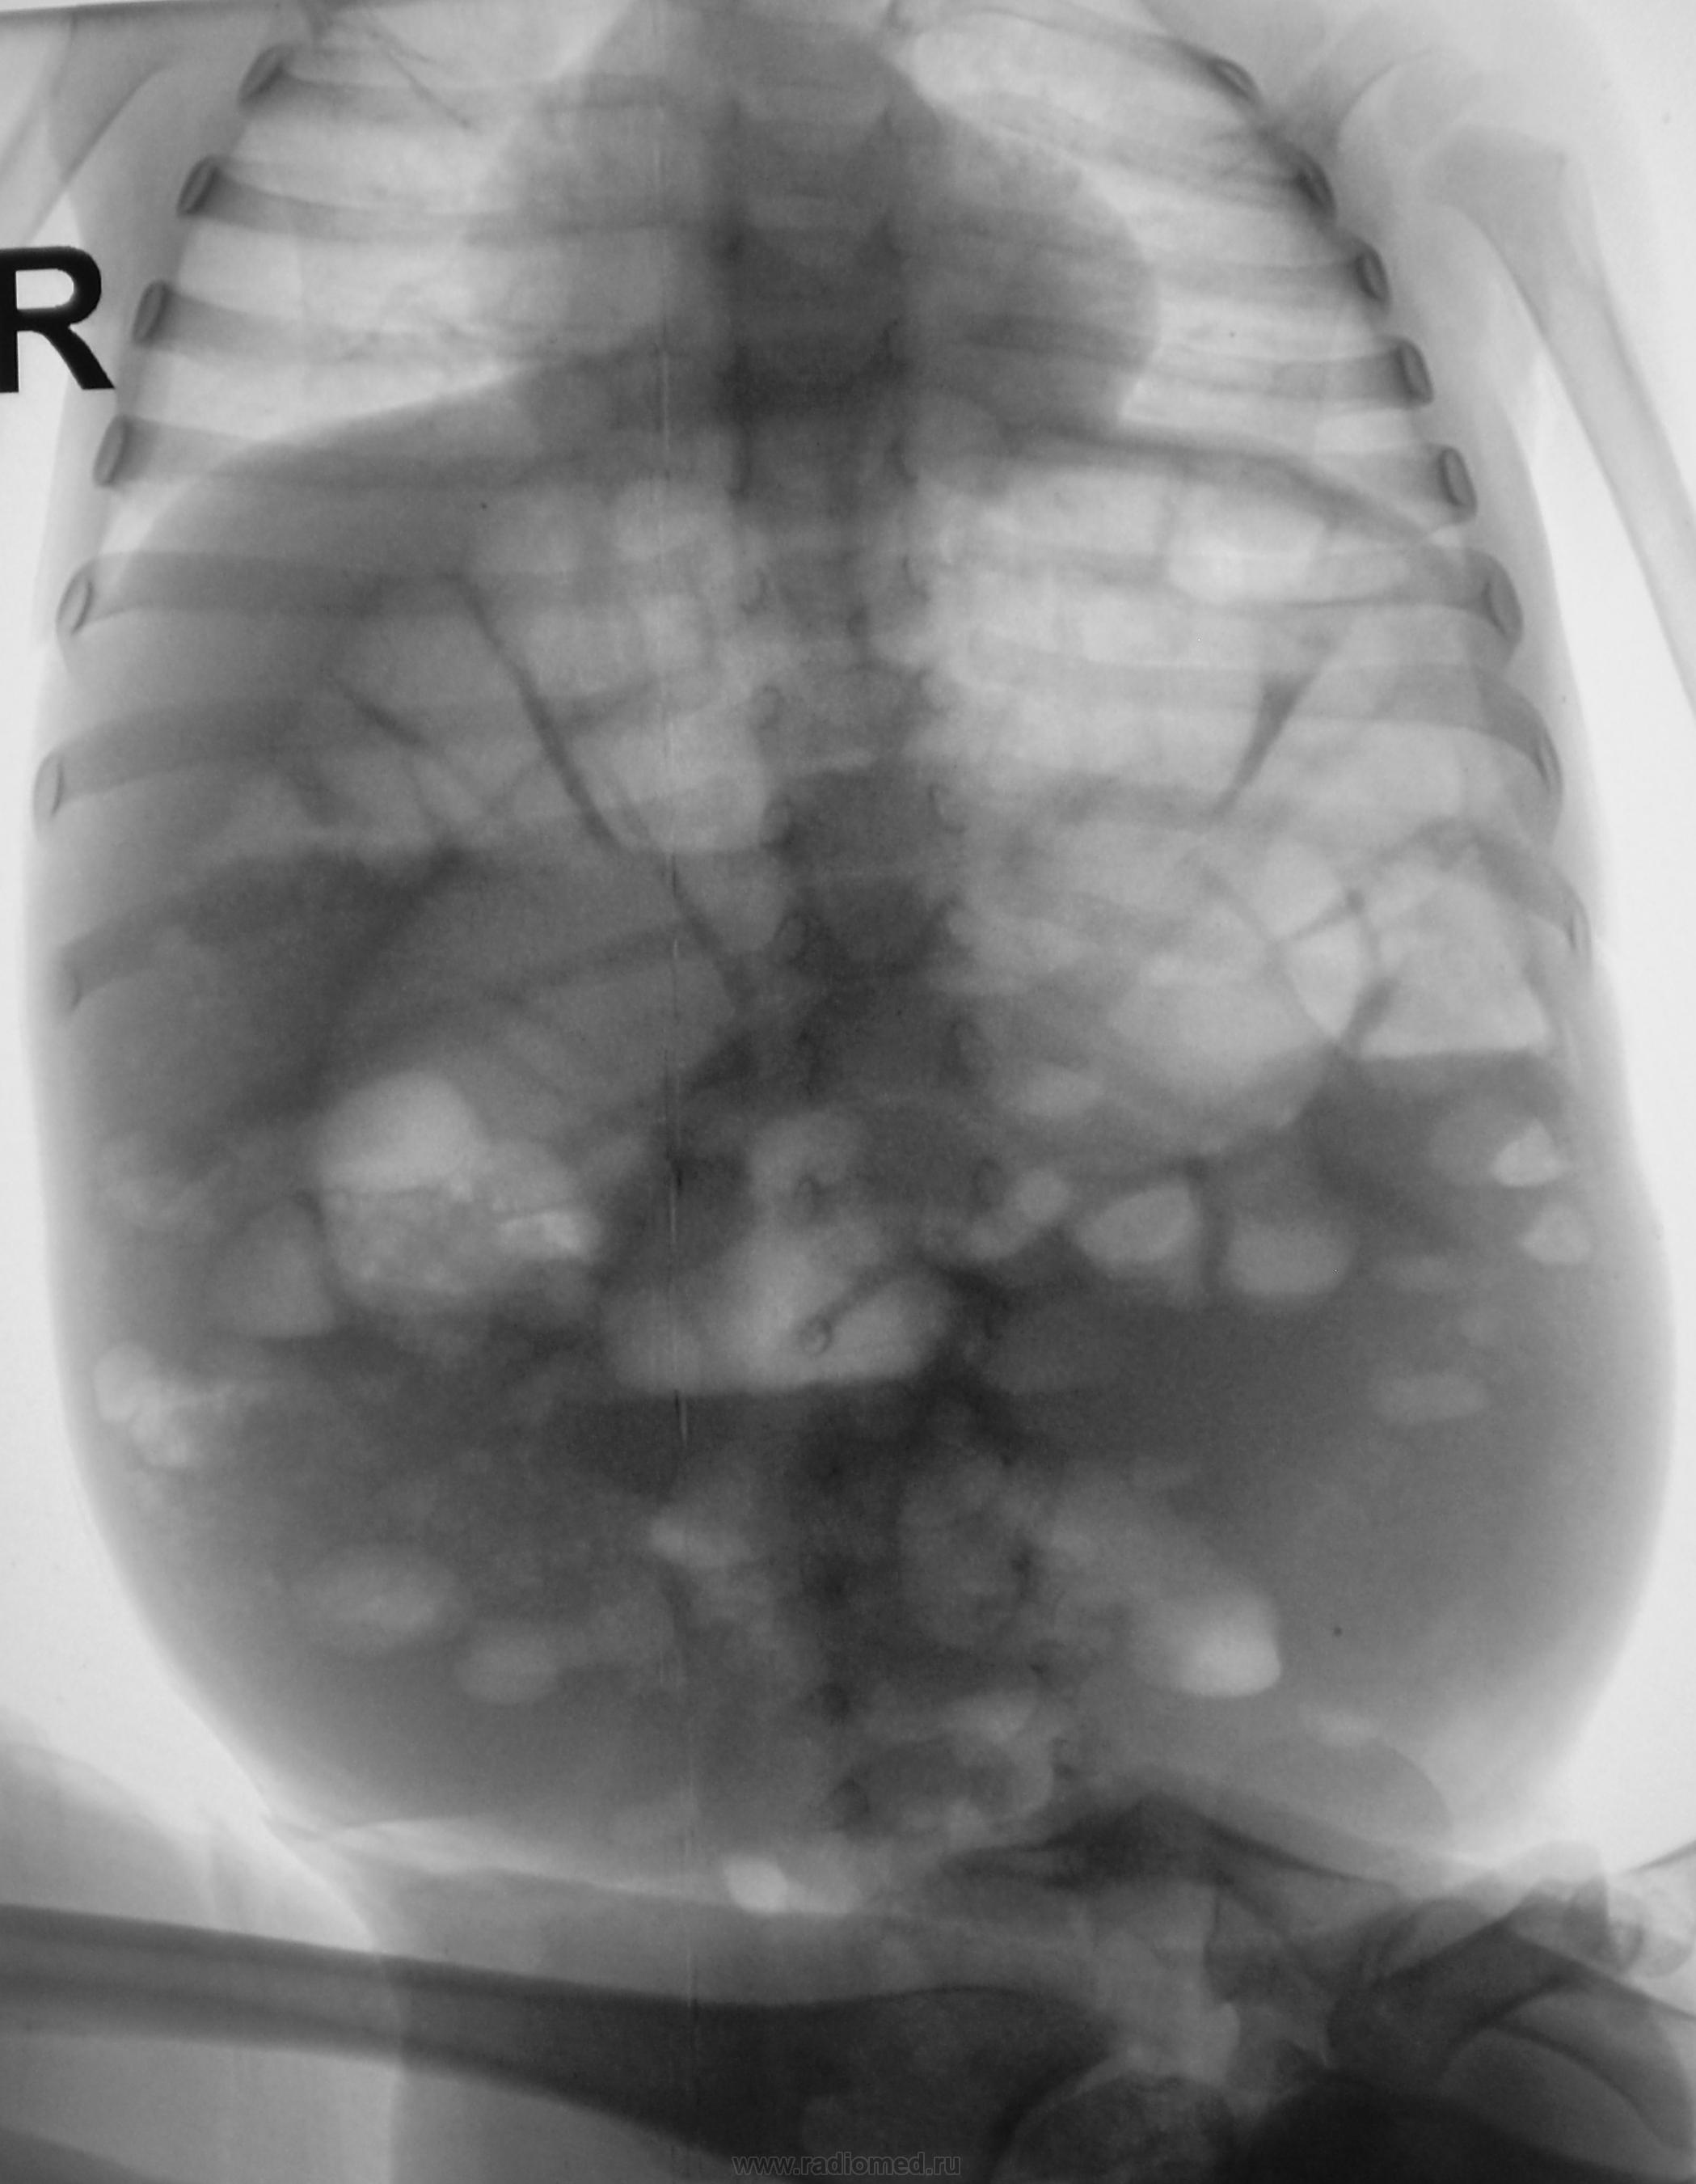

На рентгенограмме толстокишечные "чаши Клойбера". Учитывая клинику, можно думать о болезни Гиршпрунга. Показаны УЗИ, ирригография. Желательно уточнить клинику, возраст.

Возможно, я отстал от жизни - в институте-то я учился более 50 лет тому, но на представленных вариантах снимка определяются расширенные петли ТОЛСТОЙ кишки (видны гаустры и межгаустральные складки) с газом и уровнями жидкости. Именно этот скиалогический феномен назывался "чашами Клойбер(г)а", а по принадлежности к толстой кишке я и назвал их толстокишечными. В чем оригинальность - не понял.

Мне кажется, что обьем брюшной полости значительно увеличен, также резко увеличены диаметр и длина толстой кишки, очень похоже на мегаколон - вероятнее всего болезнь Гиршпрунга. Могут быть и другие причины, вплоть до банальной диспепсии, но клиника все-таки больше опять за Гиршпрунга. Хорошо бы ирригоскопию сделать, да желательно вместе с хирургом (у нас почти всегда так делается).

Видны резко расширеные петли кишечника с гаутральными перетяжками и горизонтальные уровни жидкости с шириной меньшей высоты газового пузыря.